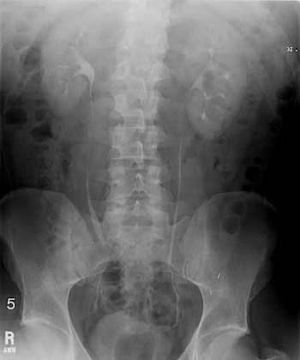

An intravenous pyelogram (IVP), also called an intravenous urogram (IVU), is a radiological procedure used to visualize abnormalities of the urinary system, including the kidneys, ureters, and bladder. Unlike a kidneys, ureters, and bladder x-ray (KUB), which is a plain (that is, noncontrast) radiograph, an IVP uses contrast to highlight the urinary tract.